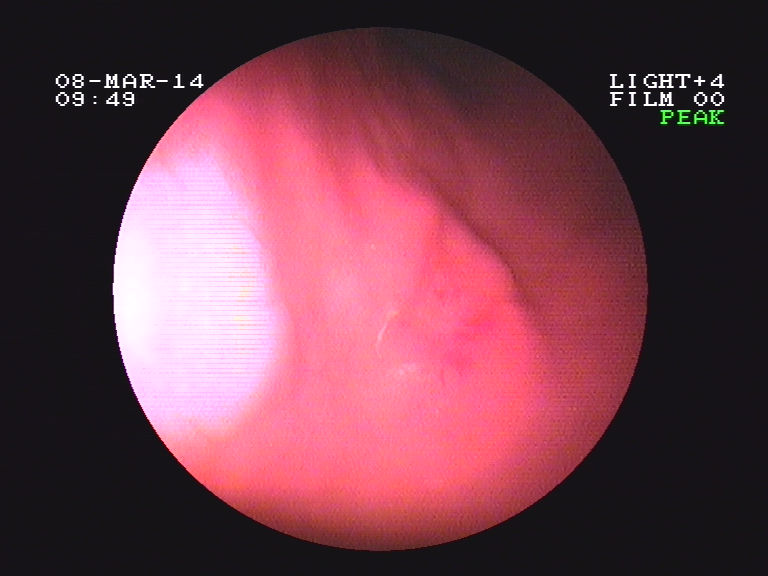

我科利用染色胃镜诊断早期胃癌1例,见附件图片。

病变染色前.bmp